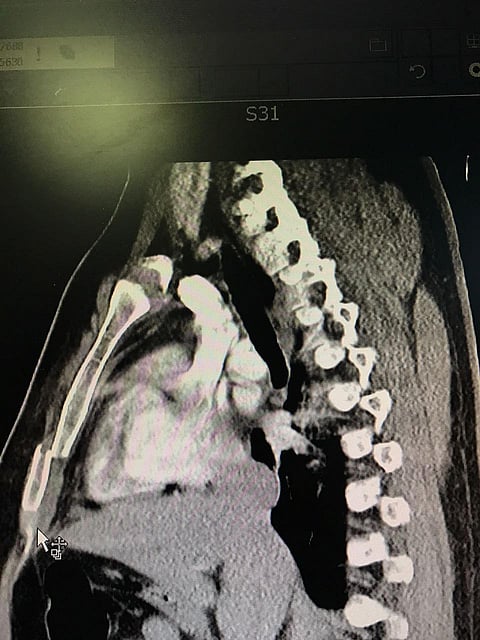

أجرى مستشفى الملك فهد بمنطقة الباحة، أول عملية من نوعها تجرى بالمستشفى لمريض سعودي يبلغ من العمر٢٣ سنة تعرض لحادث مروري أدى إلى كسر في عظمة القفص نتج عنه آلام شديدة وتشوه في الصدر مما تطلب تدخلا جراحيا عاجلا تحت إشراف مباشر من الدكتور حسن الزندي استشاري جراحة الصدر رئيس أقسام الجراحه بالمستشفى، وذلك بعمل تثبيت للكسر باستخدام شريحة مصنوعة من مادة التيتانيوم عالية التصنيع وذات جودة عالية.

وقال المتحدث الرسمي لصحة الباحة طارق الغميضي إن ذلك بداية إن شاءالله لإجراء عمليات أكثر تعقيدا لهذا النوع من التشوهات للقفص الصدري، مبيناً أن العملية استغرقت ما يقارب الساعة والنصف والمريض يتمتع بصحه جيدة ولله الحمد وفِي طور الخروج من المستشفى.